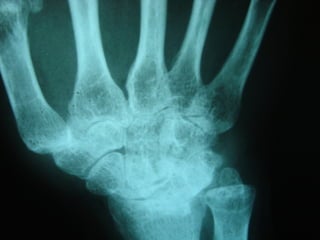

Achados radiográficosAchados radiográficos

 Osteopenia peri-articularOsteopenia peri-articular

 Diminuição do espaço articularDiminuição do espaço articular

 Presença de cisto e erosõesPresença de cisto e erosões

 Edema de partes molesEdema de partes moles

 Presença de deformidadesPresença de deformidades